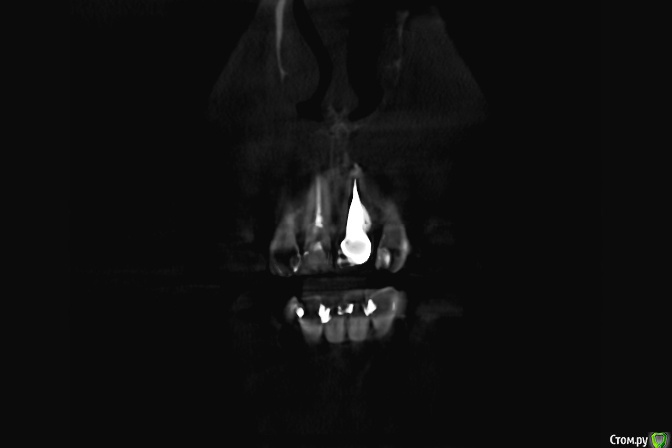

Zelenoglazka Опубликовано 24 апреля, 2017 Автор Поделиться Опубликовано 24 апреля, 2017 Сфотографировала снимок с визиографа. Распечатан на глянцевой фотобумаге, поэтому слегка бликует и отражает окружающие предметы Ссылка на комментарий

Zelenoglazka Опубликовано 24 апреля, 2017 Автор Поделиться Опубликовано 24 апреля, 2017 можно ли что-то сказать по этому снимку? Ссылка на комментарий

Zelenoglazka Опубликовано 25 апреля, 2017 Автор Поделиться Опубликовано 25 апреля, 2017 К сожалению этот вопрос можно рассматривать только при очном осмотреВчера звонила доктору, который протезировал, но только уехал и будет в городе после майских праздников. Сходила в другую клинику - доктор по снимку прокомментировал, что вкладка сделана очень глубоко, но, будем надеяться, что с зубом все будет хорошо. Проверил прикус, но там я и сама чувствовала, что иногда немного задевала нижним зубом, поэтому он подточил коронку изнутри, убрав ее из прикуса (не знаю правильно ли я выражаюсь). Посмотрел десну, постучал по этому зубу и по соседним, ничего подозрительного не обнаружил и сказал пока следить за ощущениями. Ссылка на комментарий

Zelenoglazka Опубликовано 2 мая, 2017 Автор Поделиться Опубликовано 2 мая, 2017 Здравствуйте, была в пятницу у другого доктора, сделали очередной рентген, распечатали его с увеличением на формат А4. Доктор по снимку полагает, что в кончике корня, после вкладки плохо запломбирован канал и возможен вялотякущий воспалительный процесс, отправил на компьютерную томографию для уточнения. Действительно, ортопед, ставивший вкладку, не перепломбировал канал перед этим, т.е. по панорамному снимку, который был у меня на тот момент, решил, что там все хорошо запломбировано, несмотря на то, делали это лет 17 назад. Как мне позже объяснили, в те годы были еще другие пломбировочные материалы, которые со временем рассасываются в каналах ( Вопрос такой - могу я как-то тут выложить с диска результаты кт и сможет ли кто-нибудь их прокомментировать?Доктор, направивший на кт, сказал, что, если подтвердится, то можно кончик корня удалить хирургически, сохранив остальной зуб с коронкой.К слову сейчас зуб практически не беспокоит - боли и пульсации нет, осталась только небольшая чувствительность при надавливании на верхушку корня. И некоторый дискомфорт от самой коронки, т.к., возможно, еще не совсем к ней привыкла, ощущаю как инородную во рту. Но боюсь оставлять как есть, т.к. планирую беременность и не хотелось бы потом во время беременности решать эти проблемы. Ссылка на комментарий